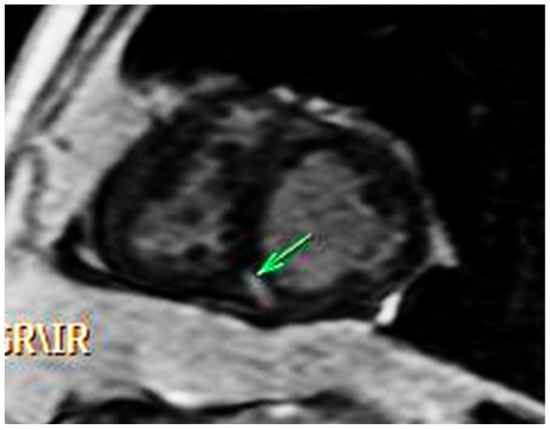

The Case of a 44-Year-Old Survivor of Unrepaired Tetralogy of Fallot, Right Aortic Arch and Abdominal Aortopulmonary Collateral Vessels

2. Case Report

2.1. Initial Work Up

2.2. Diagnosis and Management